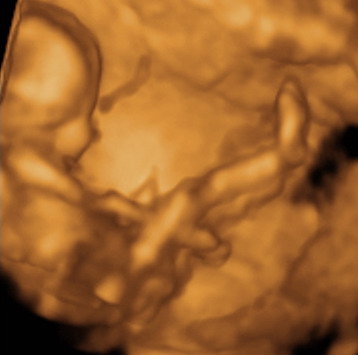

KépKép